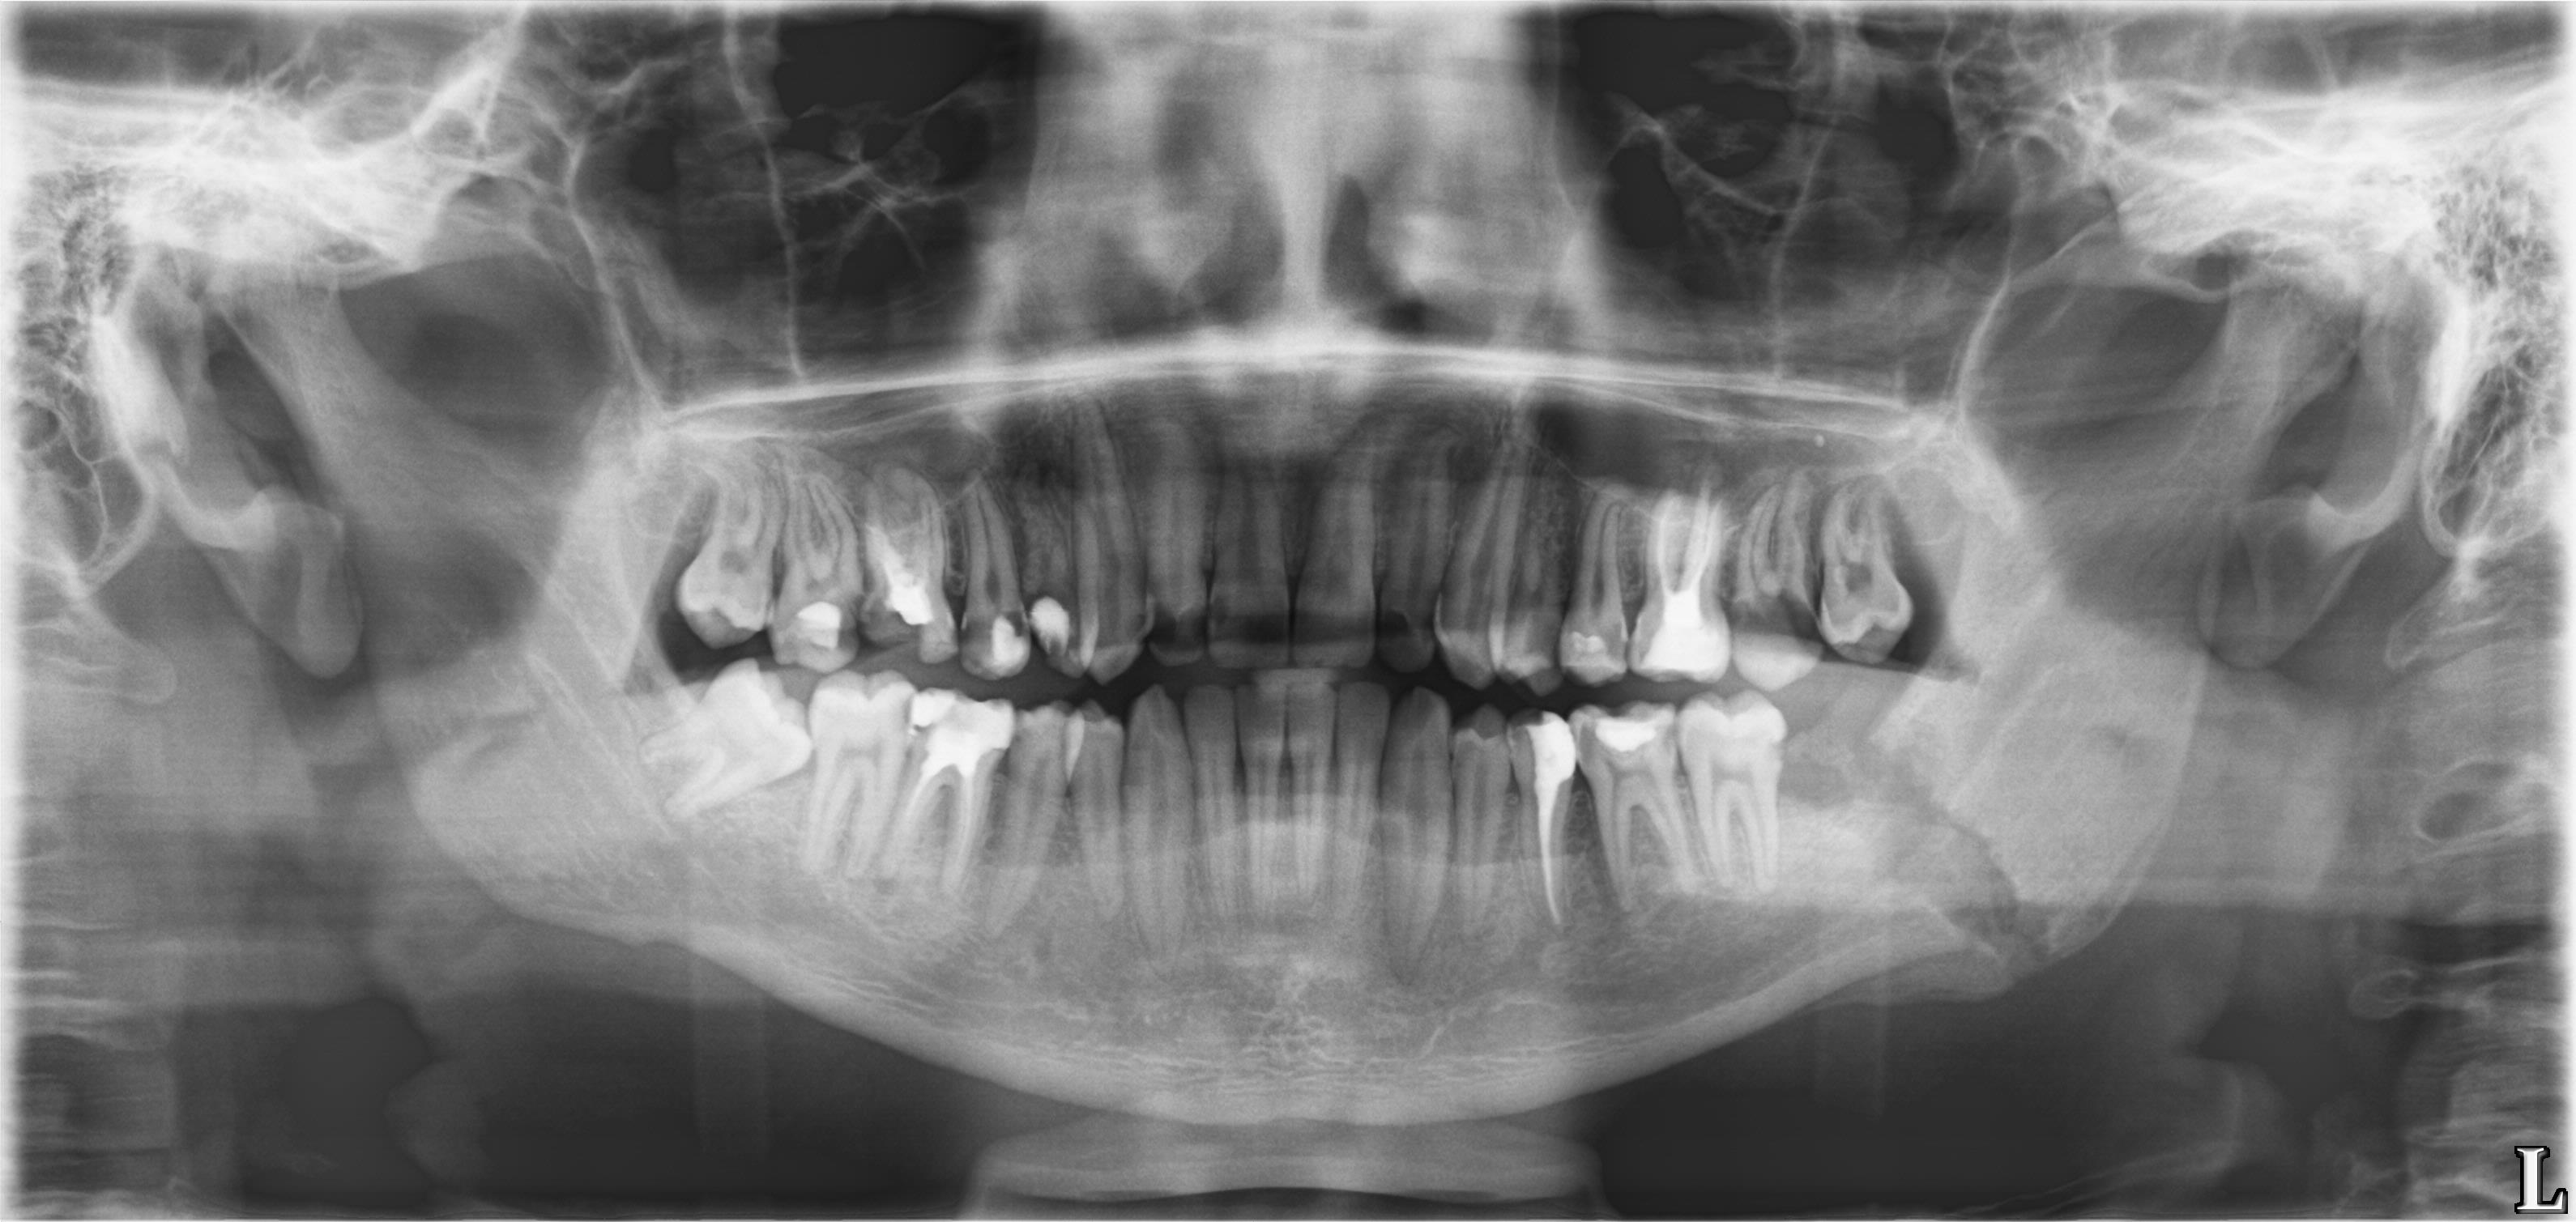

Перелом нижней челюсти

Молодой парень с припухлостью в области угла левой нижней челюсти.

Прислал ЛОР провести дифдиагноз между лимфаденитом и сиаладенитом.

--Травма была?

--ЫЫЫ. Месяц назад...